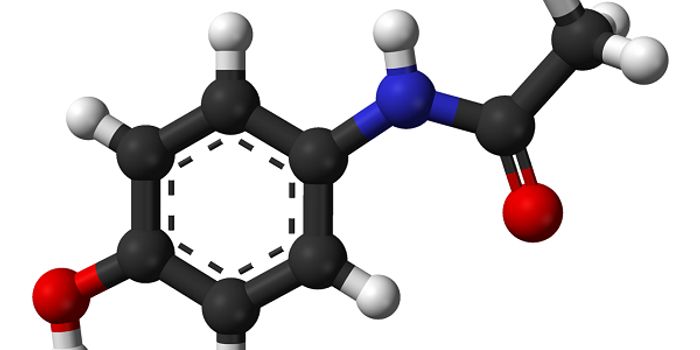

JAN 06, 2016Chemistry & PhysicsScientists are taking a closer look at the main breakdown product of aspirin, called salicylic acid, and its potential t ...

JUN 21, 2016NeuroscienceThere has been an increasing amount of attention on an interesting, legal drug known as kratom that purportes to help ea ...